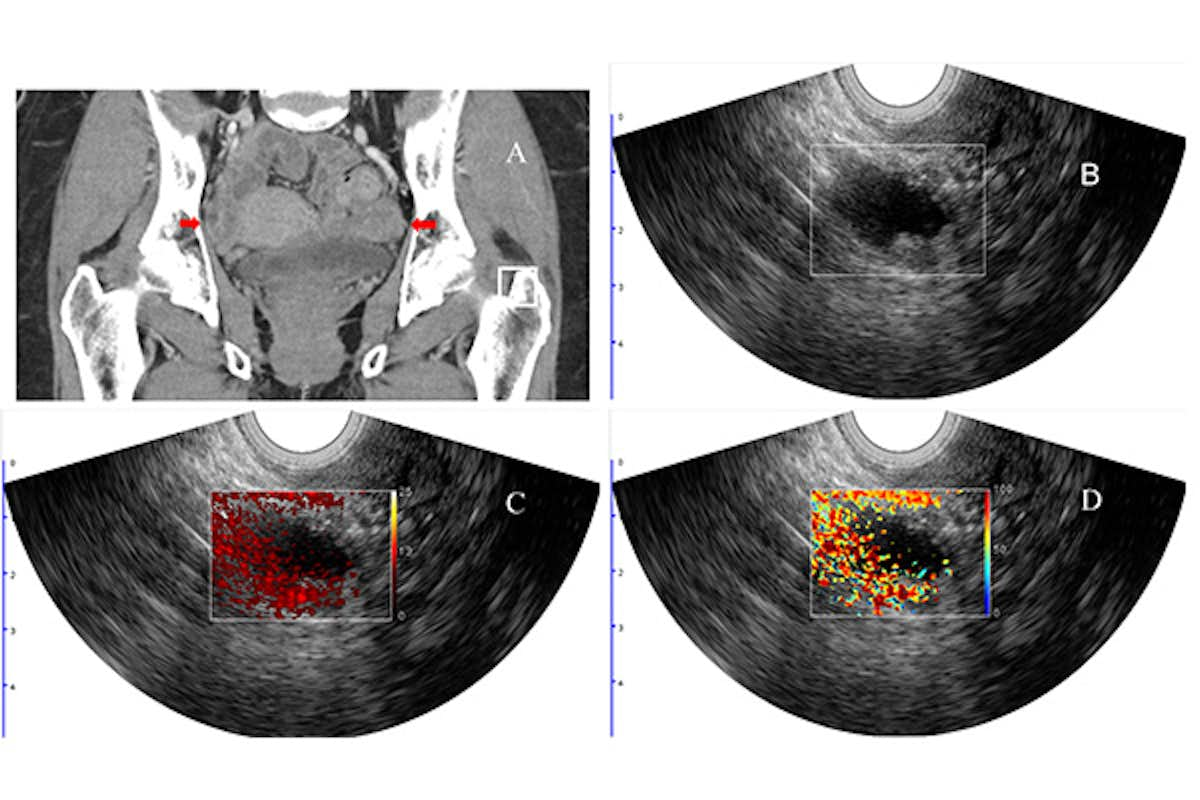

“Photoacoustic imaging combined with ultrasound provides complementary diagnostic imaging data involving structure and function,” Zhu said. “The ultrasound localizes the lesion, and the photoacoustic images inform tumor hemoglobin content and percent of blood oxygen saturation.”

Hemoglobin concentration and blood oxygen saturation provide functional information on the vasculature within the tissue as well as oxygen consumption. Malignant lesions generally have higher hemoglobin concentration due to tumor angiogenesis and lower blood oxygen saturation due to high tumor metabolism, a finding that helps differentiate benign from malignant lesions.

In a clinical study conducted by the team, 68 patients scheduled to have their ovaries surgically removed underwent clinical ultrasound as well as the combined photoacoustic and ultrasound technology (PAT/US) that Zhu’s team developed. Among the patients, 14 had malignant lesions in their ovaries or adnexal regions, two patients had malignant fallopian tubes, and 52 patients had benign lesions. Each lesion was graded by two radiologists using the Ovarian-Adnexal Reporting and Data System (O-RADS), which classifies risk for malignancy in six categories, from O-RADS 0 being an incomplete evaluation to O-RADS 5 meaning a more than 50% risk of malignancy.

When comparing the malignant and benign lesions, the relative total hemoglobin in the patients with malignant lesions in the ovaries and in the adnexal region was 1.8 times higher than in those with benign lesions. The blood oxygen saturation was 5% lower in those with malignant lesions, though it was not a statistically significant difference. Presence of the cancer antigen CA 125 was significantly different in patients with malignant lesions compared with patients with three common types of benign lesions but not significantly different from the group with endometriosis, abscess, adhesions, infarction or torsion.

Ultimately, the team found that the most important predictors of malignancy were relative total hemoglobin, the O-RADS score, presence of the cancer antigen CA 125, and percentage of blood oxygen saturation (sO2). Their model that incorporated all four features had an area under the receiving characteristic curve (AUC) of 0.97, a metric used in medical imaging diagnosis to measure a model’s performance. A score of 1 indicates ideal model performance.